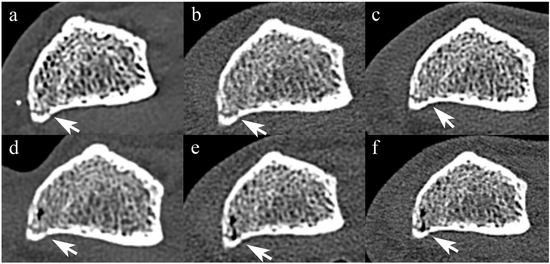

Figure 3 and Figure 4 show forearm with non-displaced fracture in STD and UHR images, respectively.

Figure 3. Comparison of STD-mode PCCT and EIDCT images of a non-displaced fracture. Images were obtained using (a) Alpha, (b) Drive, (c) X.cite, (d) Force, (e) AS, and (f) Flash scanners. The non-displaced fracture (arrow) is comparably delineated in all images.

Figure 4. Comparison of UHR-mode PCCT and EIDCT images of a non-displaced fracture. Images were obtained using (a) Alpha, (b) Drive, (c) X.cite, (d) Force, (e) AS, and (f) Flash scanners. The non-displaced fracture (arrow) is delineated more clearly in the UHR mode images than in STD mode images.

When the scan mode was standardized, PCCT yielded higher median scores than all EIDCT scanners in UHR mode, but there was no statistically significant difference between PCCT and EIDCT in either resolution (STD, p = 0.23; UHR, p = 0.063; Table 7). Inter-reader agreement in fracture visibility scores among three interpreters was 0.86 (95% CI, 0.65–0.96; p < 0.001).